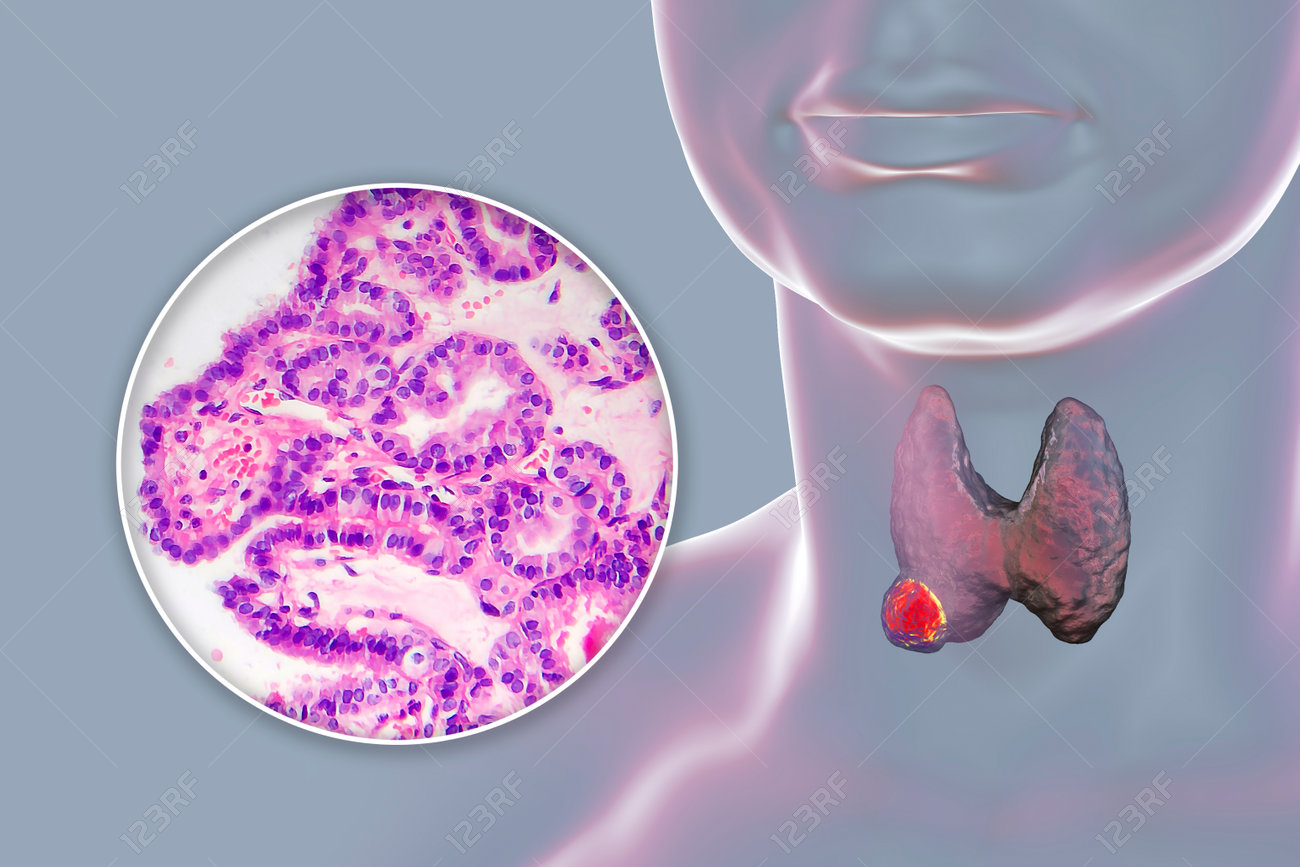

3d, anatomy, biology, biomedical, cancer, carcinoma, cell, cellular, clinical, composite, diagnosis, diagnostics, disease, education, endocrine, examination, gland, growth, health, healthcare, histology, histopathology, illustration, imaging, light micrograph, lm, male, malignant, man, medical, medicine, micrograph, molecular, morphology, neoplasm, oncology, papillary, pathology, proliferation, research, scientific, skin, structure, thyroid, tissue, transformation, treatment, tumor, visualization,